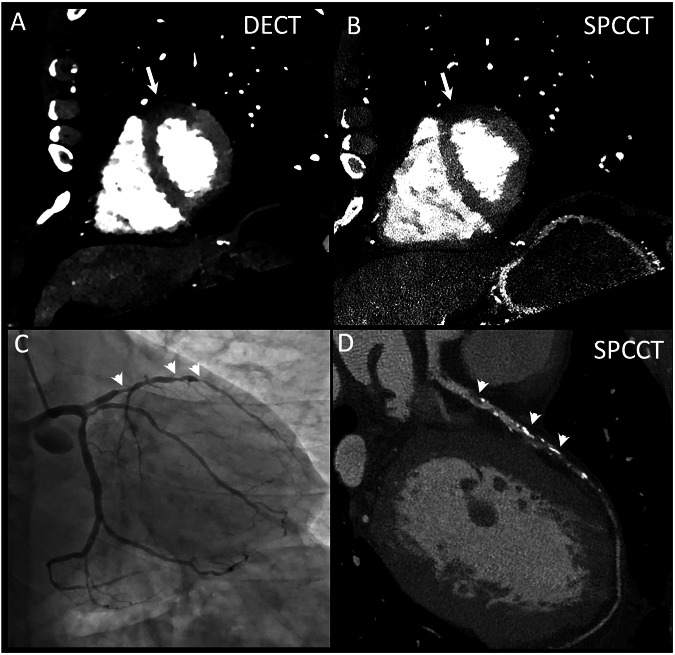

Background: Spectral photon-counting computed tomography (SPCCT) outperformed dual-energy computed tomography (DECT) for coronary artery stenosis assessment. However, data about myocardial perfusion imaging (MPI) is lacking. This feasibility study aimed to evaluate and compare the diagnostic performance of SPCCT and DECT for rest MPI in patients with hemodynamically significant coronary stenoses, using invasive coronary angiography (ICA) and invasive fractional flow reserve (FFR) as reference standards.

Materials and methods: Eighteen very-high-risk patients with hemodynamically significant coronary stenoses at ICA underwent both dual-layer DECT and SPCCT coronary CT within three days. The sensitivity, specificity, and accuracy of MPI in detecting myocardial hypoperfusion were assessed. Quantitative attenuation differences between normal and hypoperfused myocardial segments were compared for both modalities. Interobserver variability was assessed with a weighted kappa analysis.

Results: SPCCT demonstrated comparable overall performance to DECT for MPI, with an overall sensitivity, specificity, and accuracy of 73.3%, 79.2%, and 76.9%, respectively, versus 73.3%, 75%, and 74.4% for DECT. SPCCT outperformed DECT in the left anterior descending artery territory, achieving a sensitivity of 87.5%, specificity of 100%, and accuracy of 90%, versus 62.5%, 50%, and 60% for DECT. For each CT system, attenuation analysis revealed differences between normal and hypoperfused segments, with mean differences of 17.9 HU for DECT and 15.8 HU for SPCCT (p < 0.05). Inter-reader agreement was higher for SPCCT (κ = 0.86) compared to DECT (κ = 0.62).

Conclusion: SPCCT and DECT provided similar diagnostic performance for rest MPI in a very-high-risk patient cohort, demonstrating comparable effectiveness in detecting the effects of hemodynamically significant coronary stenosis.

Relevance statement: Hemodynamically significant stenosis in very-high-risk patients results in myocardial hypoperfused areas at rest that can be detected equally well with dual-layer CT and spectral photon counting CT, albeit with better reproducibility for the latter.

Key points: SPCCT and DECT showed comparable performance for MPI at rest in very-high-risk patients. The differences between normal and hypoperfused segments were of 17 HU and 16 HU on conventional images for DECT and SPCCT. SPCCT showed higher interobserver agreement compared to DECT, suggesting improved reproducibility.